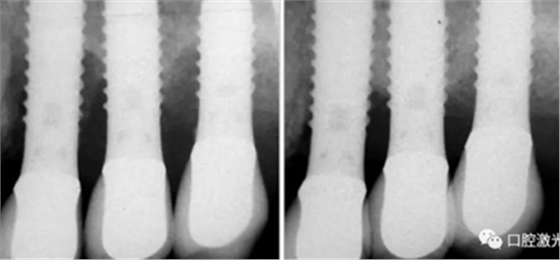

激光辅助种周炎手术治疗前,中和手术后4年